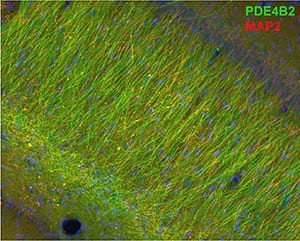

Atkins-PDE4B2-in-Hippocampal-Dendrites-300